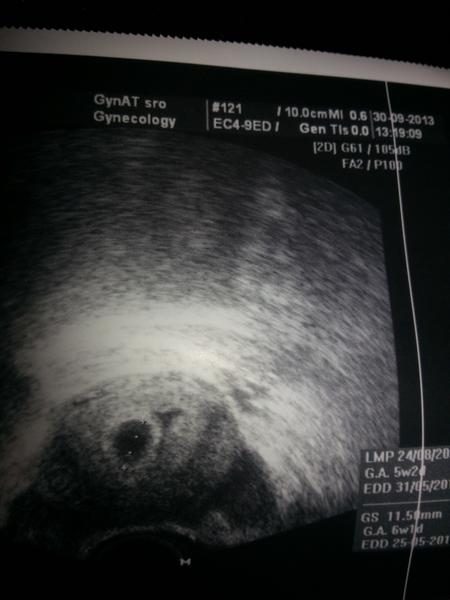

Babulky ahojte.Tak ja koncim I.trimester,este tyzden uzivania Utrogestanu,snad tie nastavajuce dva prebehnu bez komplikacii.Prikladam foto,zoznamte sa s nasim drobcekom 😉 Prva foto je na potvrdenie tehu a tato druha z prvej poradne minuly tyzden,srdiecko bilo ako zvon.Zuzi bude aj tvojmu neboj sa!

@jankaferancova Ahoj Jani, podávam najnovšie správy, cez víkend som opäť špinila, tak som dnes letela k lekárovi a aké prekvapko ma tam čakalo. 1 cm bábätko s krásnym bijúcim srdiečkom. Som až plakala od radosti, že je všetko tak, ako má byť. 🙂 A dostala som už aj tehotenský preukaz. Od zajtra začínam oficiálne končím 7 týždeň a začínam 8. 🙂 A o dva týždne ma čaká prvá poradňa. 🙂